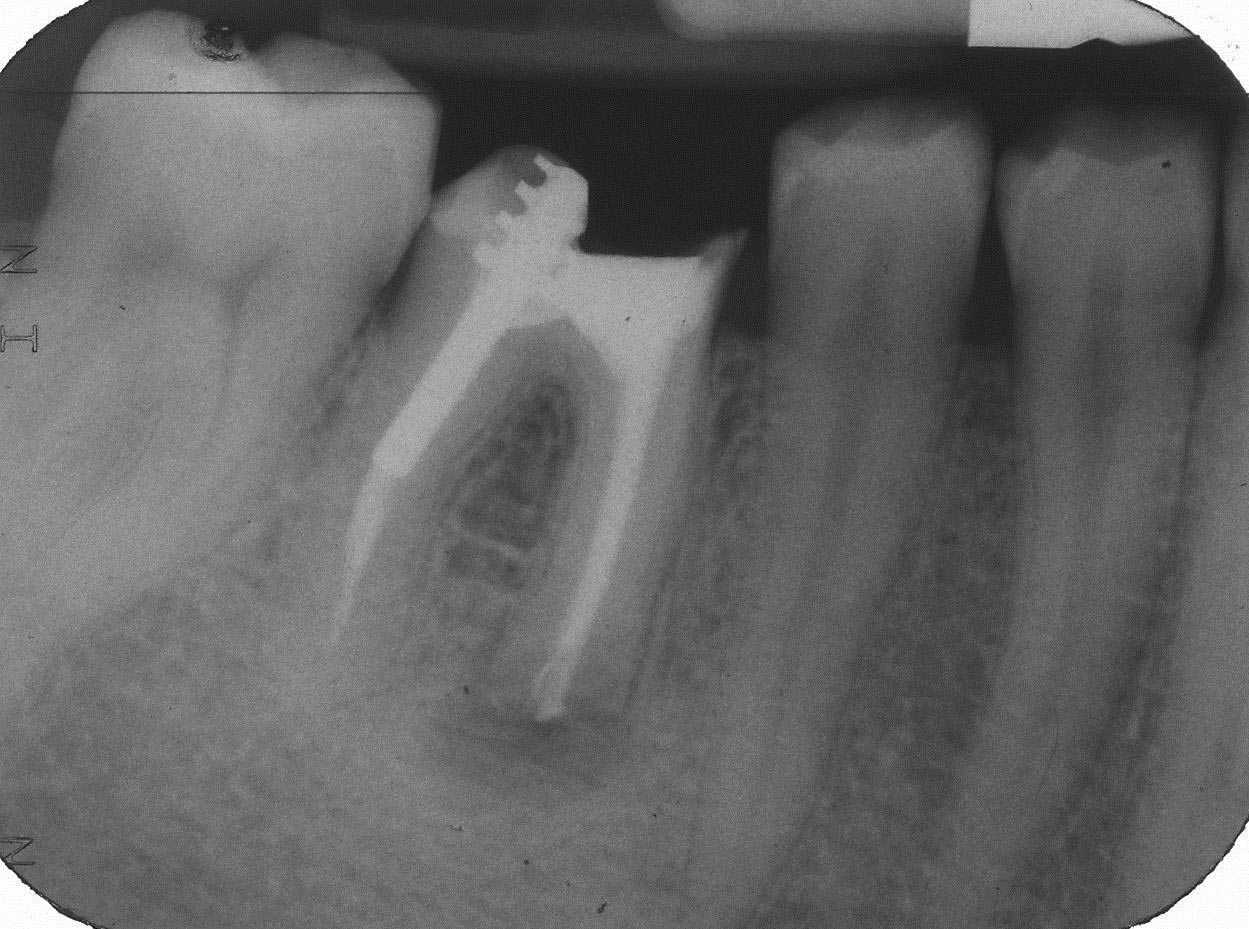

FL-3 Veröffentlicht 6. Oktober 2013 am 1249 × 929 in Teilrevision Zahn 46 – Wie würden Sie entscheiden?